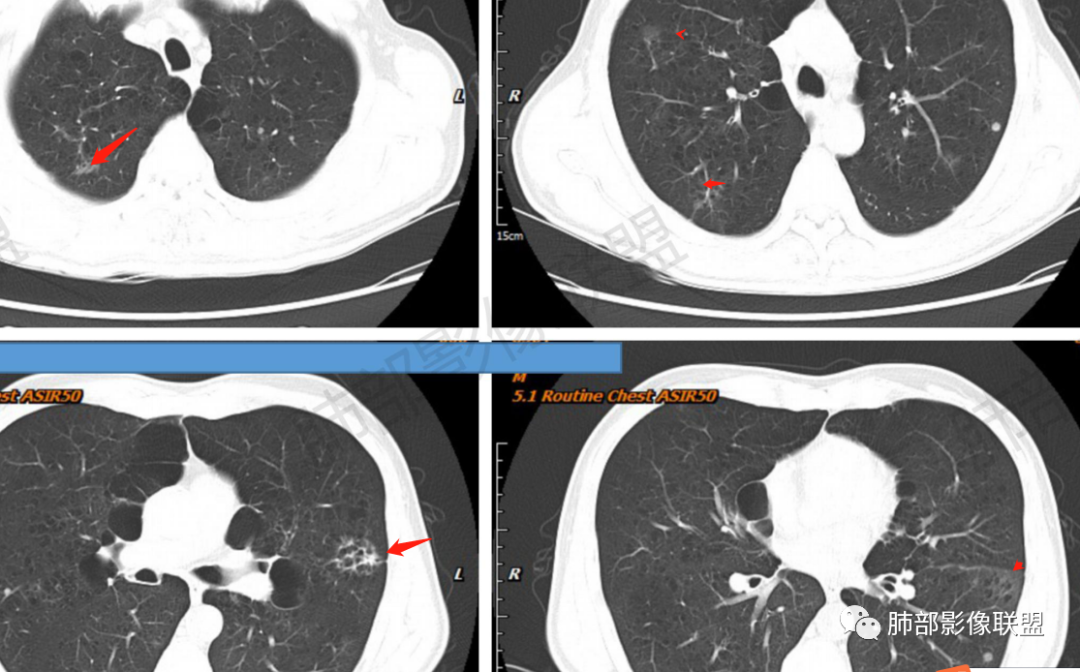

琦遇:恶性没有问题,肺气肿底子、病灶分叶、少许毛刺、叶间胸膜凹陷、部分边缘可见清晰的GGO、胸膜牵拉凹陷、局部胸水、近端支气管截断、部分支气管被推移、占位效应明显、强化特点为不均匀强化、内部有少许沼泽样低强化区,强化部分轻中强化为主、余肺可见转移性结节、左肺上叶似为囊腔型腺癌一枚,肿瘤标志物提示非小、神经内分泌,综合分析考虑大神泌、腺癌、腺鳞癌、鳞癌  同时左肺上叶囊腔型腺癌  肺转移

傅昌瑜:中老年男性,肺气肿背景,右胸背疼痛1周。CEA、NSE、CYFRA—211升高。左上肺混合磨玻璃结节,内见较多空泡和扩张支气管。左下肺胸膜下肿块,边缘较光滑,深分叶,似有血管进入,与支气管关系不清,内见不均匀强化,见沼泽地样坏死,有胸膜栽赃。另两肺多发圆形小结节。考虑恶性并肺内转移,多原发可能性大,左上肺腺癌,左下肺病理难以判断,小细胞癌?鳞癌?

小锁:中老年男性,肺气肿背景,右胸背疼痛1周。CEA、NSE、CYFRA—211升高。左上肺混合磨玻璃结节,边界清楚,内见较多空泡。左下肺肿块,边缘清楚,深分叶,有血管和支气管进入,胸膜凹陷。另两肺多发圆形小结节。考虑双发原位癌,左上肺腺癌,左下肺大神泌或腺鳞癌可能,肺内转移。

蓝天白云:中年男性,肺气肿背景,左肺下叶肿块,边缘膨隆,有分叶,内有湖泊样坏死,有轻中度强化,局部胸膜栽赃,收缩力不强,周围见肺气肿征象。左肺上叶混合磨玻璃影,边界清楚,考虑都是恶性,左上肺iac,左下肺腺鳞癌,或大细胞肺癌可能。两肺多发结节,考虑转移

毛勤香:老年男性,肺气肿背景,左肺下叶肿块,分叶,边缘光滑,土豆块样,细支气管闭塞,增强轻度不均匀强化,似有坏死,左肺另见多发结节,淋巴结未见明显肿大,恶性确定,吸烟史,鳞癌破坏力强,侵袭力差,多原发的一般很少多于3个,故排后,首先考虑神经内分泌癌,局部血管穿行,鉴别淋巴瘤

周太狼:中年男性,吸烟、高血压史,肿瘤指标升高,肺气肿背景下,左肺下叶肿块影,分叶、膨隆、未跨叶裂,支气管截断,不均匀强化。另双肺多发结节及磨玻璃影,左肺上叶混合磨玻璃,内可见多发空泡影。整体考虑恶性,肺癌伴肺内转移,左下肺鳞癌?神经内分泌癌?左肺上叶囊腔腺癌?

LCNEC最常见的影像特征包括:(1)肿块发生部位:周围型肺癌为主,少数发生于肺中央。(2)肿块大小及形态。因肿瘤细胞生长迅速常形成较大肿块,因此其体积一般较大,直径常在3~10cm范围内,病灶常为不规则形软组织肿块。(3)肿块边界。多数学者报道大多数肿块边界清晰,边缘呈分叶状,毛刺征及“胸膜凹陷征”少见,认为与该病对周围组织浸润较轻及较少产生纤维瘢痕组织牵拉有关联。(4)肿块密度、强化特点及代谢情况。据文献报道,该类肿瘤因体积较大CT上常见软组织肿块,且多数密度不均匀,内见囊变坏死区,增强后呈轻或中度不均匀强化(可见强化者占75.7%),认为其强化特点与其内部肉眼可见坏死灶和肿瘤较大直径有关。(5)伴随症状及远处转移。该病恶性程度高,侵袭性强,常侵犯邻近结构,如胸膜、心包、邻近骨质或纵隔内组织等,易出现纵隔淋巴结转移,部分发生肺内及远处转移,少数早期可出现广泛远处转移。